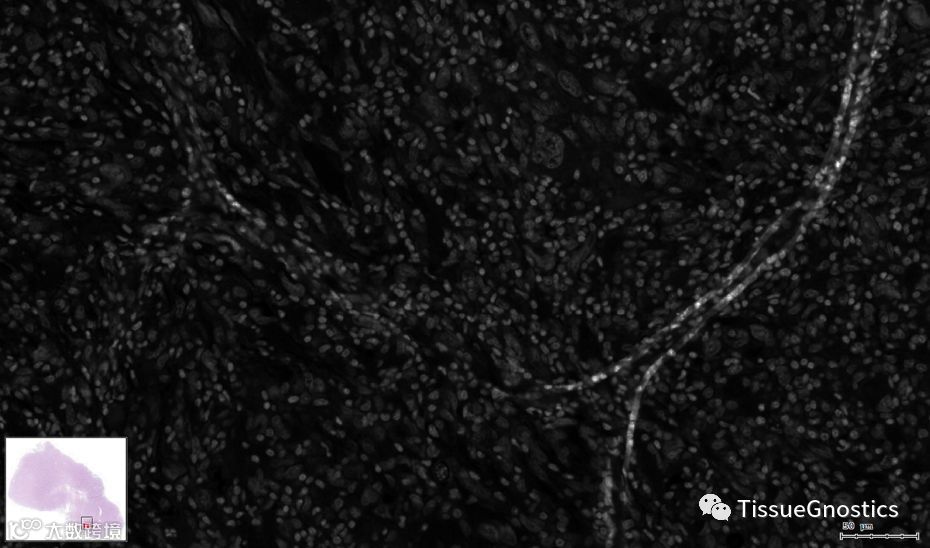

原始影像

苏木素染色通道